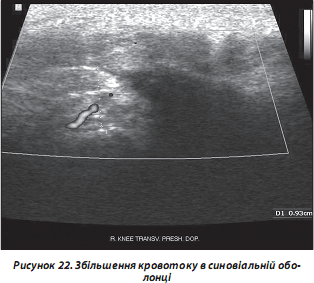

в) кровотік у синовіальній оболонці (рис. 22);